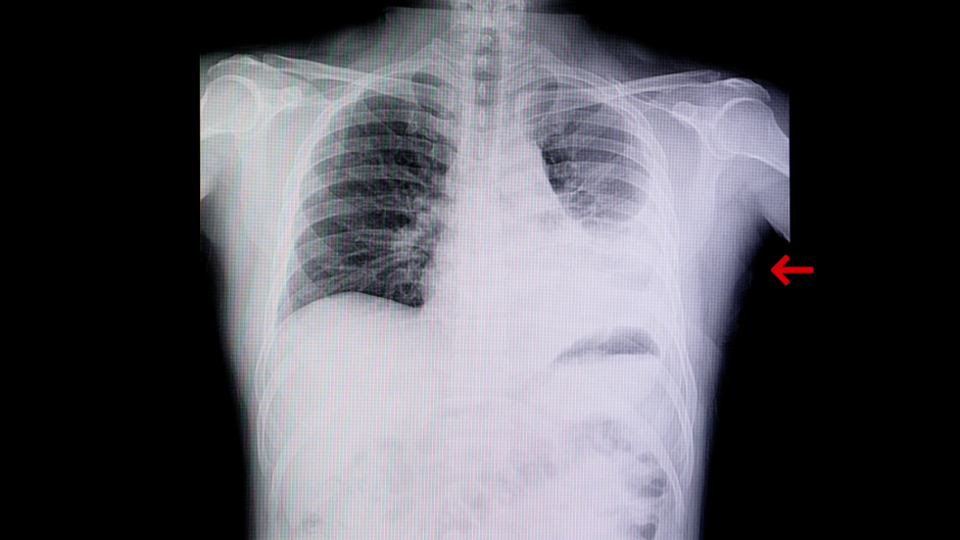

Aşılamanın pandemi zincirini kıracak en büyük silah olduğunun altını çizen Prof. Dr. Turan, aşı olmayan genç hastaların da yoğun bakımlarda görüldüğünü ve çok yoğun akciğer enfeksiyonu gözlemlendiğini söyledi. Turan, ayrıca şu an tüm dünyada görüldüğü gibi Türkiye’de de Delta varyantının aktif bir şekilde görüldüğünü ve bulaş oranı diğer varyantlara göre daha yüksek olduğu için bir an önce aşı olmayan vatandaşların aşılarını olması gerektiğini ve kişisel önlemlerin de aynı şekilde devam etmesi gerektiğini vurguladı.

Aşılamanın pandemide çok önemli bir kurtuluş yolu olduğunun altını çizen Prof. Dr. Turan, “Pandemi sırasında elimizdeki en önemli silahın aşı olduğunu vurgulamıştık ve vurgulamaya da devam ediyoruz. Çünkü ağır hasta sayısını ya da hastaneye yatış oranlarını aşılamadaki başarı belirliyor. Biz de son zamanlarda gelen hastaların çoğunlukla aşısız olduğunu görüyoruz bu da bizi çok fazla üzüyor. Aslında elimizde aşı gibi ağır hastalıktan koruyacak bir silah varken onu kullanmamış olmanın yoğun bakımda oluşturduğu yansıma gerçekten içler acısı. Çok daha genç hastalar, aşılanmamış grup çok büyük akciğer enfeksiyonuyla karşımıza geliyor. Şu an en büyük sıkıntımız, aşılanmamış grubun yoğun bakım ihtiyacının olması ve devam etmesi. Örneğin aşılanmamış bir birey gidip bu hastalığa yakalandıysa bize söylediği, ‘Çok pişmanım şu hale gelmekten dolayı, keşke aşılansaydım’ şeklinde hava açlığı içerisinde yaşamanın sıkıntısını fark ediyorlar. Bu çok önemli, büyük bir çoğunluğu aşısız grup oluşturuyor. İkinci bir grup ise iki doz Sinovac aşısı olmuş ama üzerinden fazla vakit geçmiş hastalar. Burada biz aslında Bilim Kurulunda 6 ay gibi bir süreden bahsetmiştik. 3 ila 6 ay geçmiş bireylerde özellikle bir hatırlatma dozunun yapılmasının gerekliliği söz konusu. Halkımızın bu konuda ilgisinin devam etmesi lazım. ‘İki doz aşı oldum, artık gerek yok’ gibi bir mantık yok. Çünkü hala aşılanmaya ihtiyacımız var” ifadelerini kullandı.